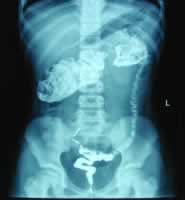

腹部CT扫描显示:左上腹胃脾间中空混杂密度占位性病变,壁厚薄不均,壁内见点状高密度影(见图1)。病变强化不明显。上消化道钡餐造影及钡灌肠显示:结肠脾曲管腔狭窄,轮廓不规则,边缘毛糙,与正常肠管分界清楚(图2)。影像诊断为结肠病变,结肠癌?手术见结肠脾曲处为实性肿瘤,围绕肠壁半周。病理报告为结肠黏液腺瘤(部分呈印戒细胞癌)。